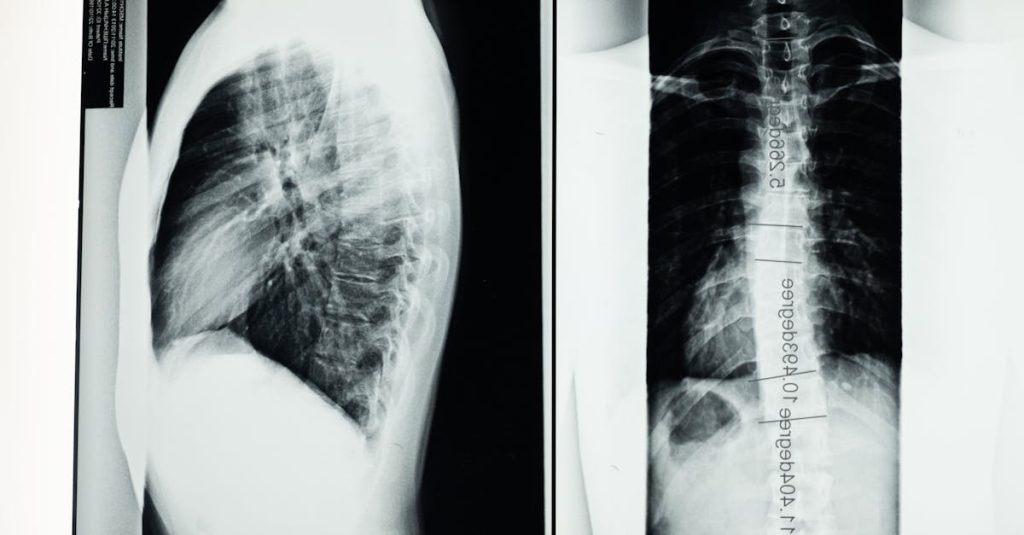

Quels examens permettent de diagnostiquer la sciatique?

Une IRM ou une radiographie est généralement nécessaire pour confirmer la cause de la sciatique.